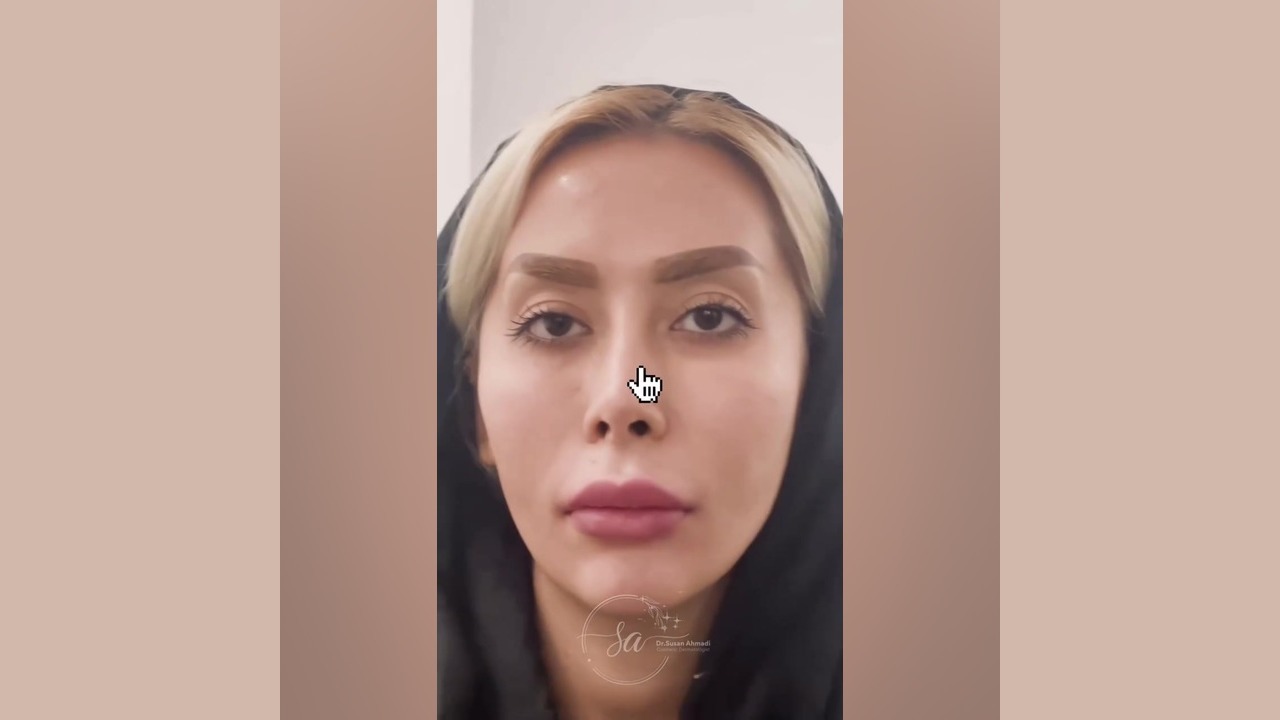

ویدیو تغییر شگفتانگیز: قبل و بعد از تزریق

برای مشاهده نتایج شگفتانگیز تزریق زیر چشم توسط دکتر احمدی، میتوانید ویدیوی قبل و بعد از تزریق را در [لینک ویدیو] مشاهده کنید. در این ویدیو، میتوانید تغییرات چشمگیر در ظاهر بیماران پس از انجام تزریق را مشاهده کنید.

دیدن این تغییرات میتواند به شما در تصمیمگیری بهتر کمک کند و انتظارات واقعبینانهای از نتایج این روش داشته باشید.